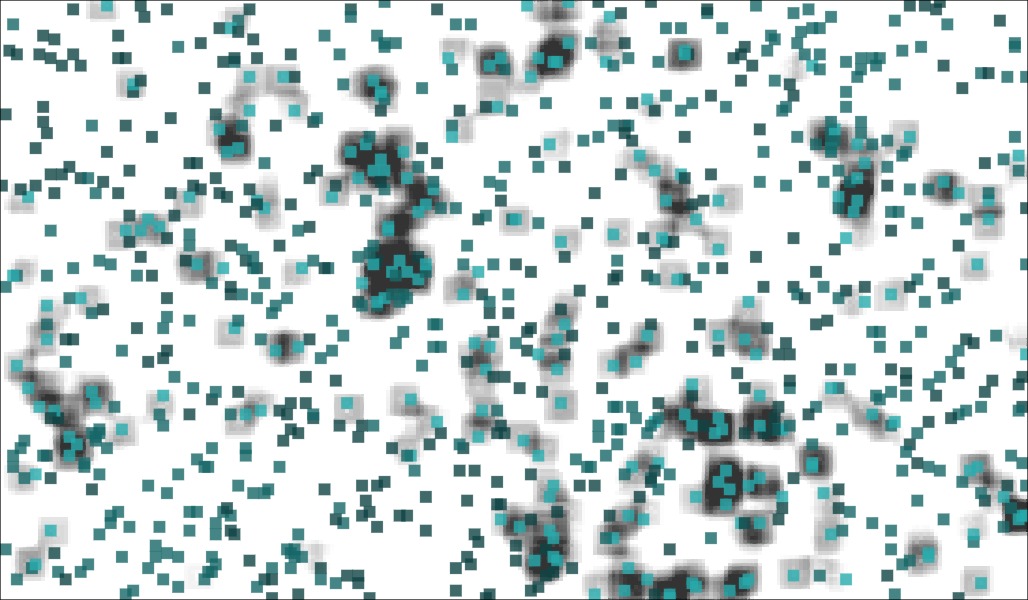

- Cellular systems and tissues (tumors, organoids,...)